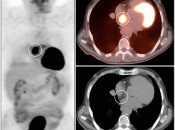

LHIAS is focal fatty infiltration of the inter-atrial septum of the heart.  It behaves as hypermetabolic brown fat, and is often intensely FDG-avid, appearing mass-like on the PET images.

Diagnosis of this hypermetabolic PET finding is confirmed by the presence of only fat on the co-registered CT images.

Although benign, we recommend mentioning this finding in the body of the report, as it often looks impressive on the PET images and can prompt a call from a clinician concerned that you “missed” a mass.